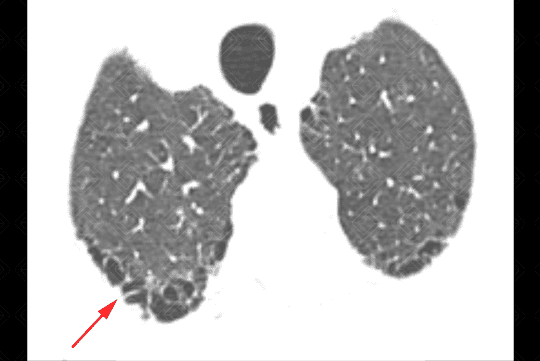

Descrição das figuras 3, 4, 5 e 6: Tomografia computadorizada do tórax seguida de aquisições coronais, sagitais e axiais mostrando as extensas áreas de enfisema centrolobular dispersas pelo parênquima pulmonar (setas vermelhas).

• Tomografia computadorizada do tórax: Este método é mais sensível e específico que a radiografia de tórax na avaliação do enfisema. Tem sido empregado para detectar, quantificar e caracterizar a doença. A tomografia é capaz de diferenciar os vários tipos de enfisema, que pode ser classificado, de acordo com a região do ácino acometida, em proximal (centrolobular ou centroacinar - figuras 3, 4, 5, 6, 9, 10 e 11 ), distal (parasseptal - figuras 7, 8, 9, 10 e 11 ) ou todo ácino (panacinar ou panlobular).